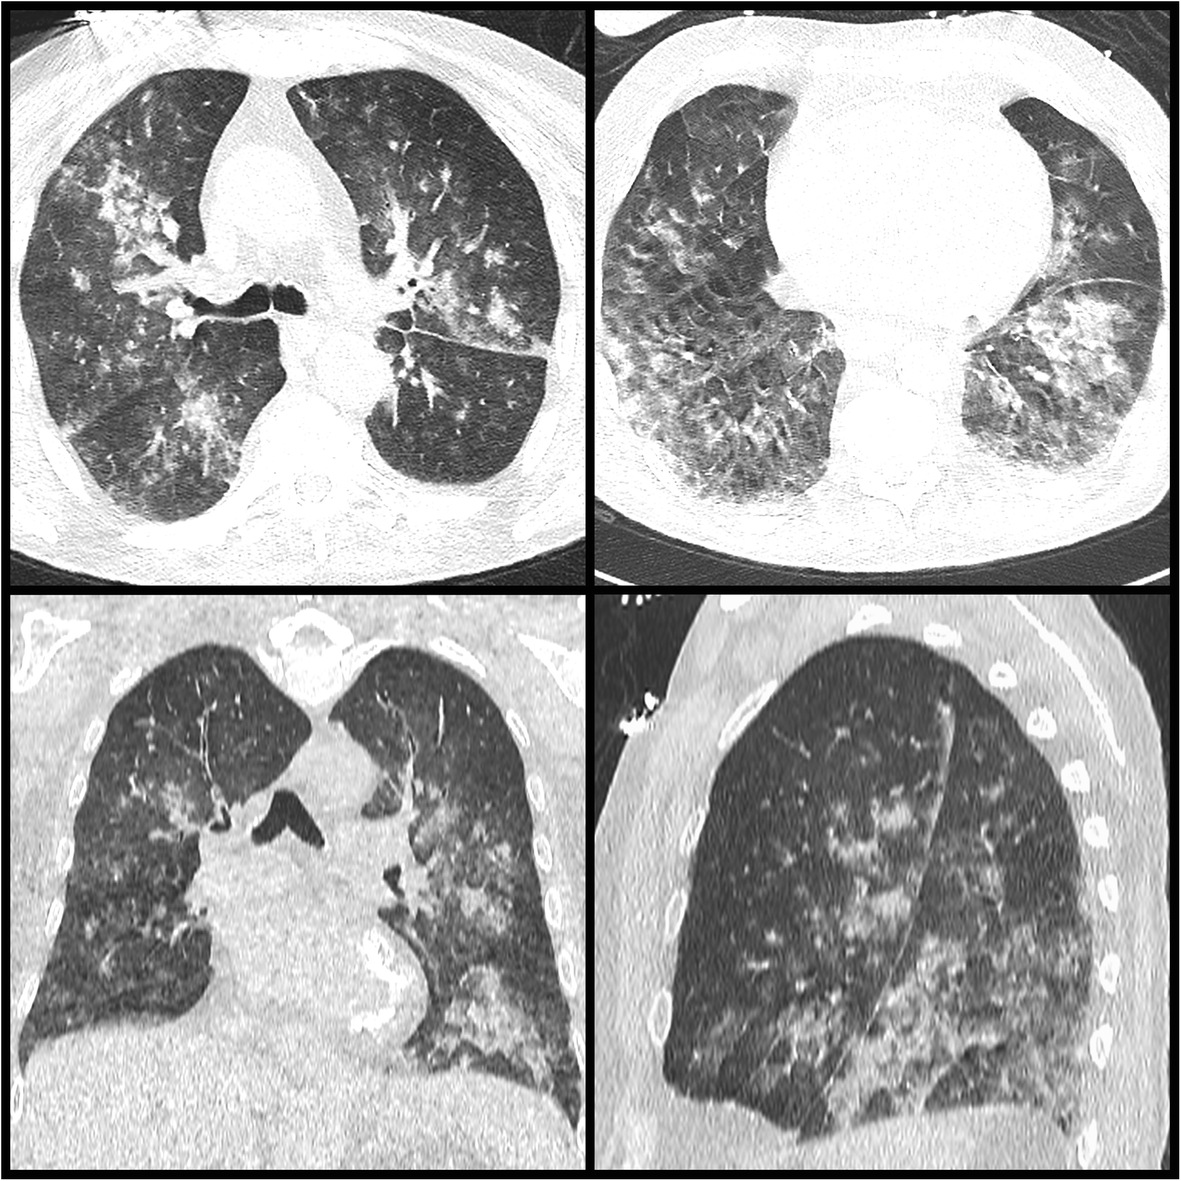

Fig. 2

From: Successful management of zinc phosphide poisoning—a Hungarian case

Chest CT-scan image of the patient on day 1. Axial, coronal, and sagittal plane CT images of the lung, with a 3-mm slice width made by Siemens Somatom Definition Device. Alveolar atelectasis from base to apex